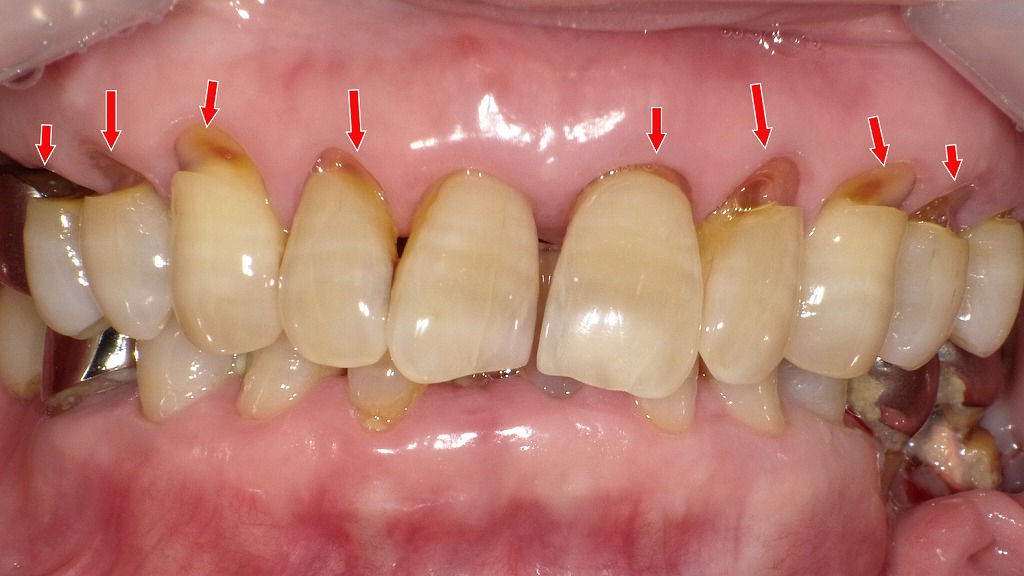

この画像は、右側の上下顎を側方から撮影した口腔内写真です。以下のような特徴と臨床的考察が見られます。

🦷 全体の所見

- **上下の犬歯から小臼歯部にかけての歯頚部(歯と歯ぐきの境目)に楔状欠損(くさび状の欠け)**が多数認められます。

- 欠損部にはCR(コンポジットレジン)修復が施されています。これは歯の色に近い樹脂素材で、欠けた部分を補う治療です。

🔍 詳細な観察ポイント

- **右上犬歯(3番)および右下第一小臼歯(4番)**では、レジンの「脱離」(剥がれ)が確認できます。

→ レジンが取れて歯質が露出し、象牙質が見えている状態です。 - **その他の歯(右上4番・5番・6番、右下2番・3番・5番・6番など)**には、レジン充填が維持されていますが、やや変色やマージンの劣化が見られます。

⚙️ 脱離の原因

- 歯ぎしり(ブラキシズム)や食いしばりによって、咬合力が歯の頚部に集中。

- 歯頚部は構造的に応力が集中しやすく、さらにレジンと歯質の境目に微小な動きが生じることで接着界面が剥がれやすくなります。

- 繰り返される応力や温度変化(飲食など)による膨張・収縮も脱離の一因です。

💡 今後の対応

- 脱離部位は再修復(再充填)が必要。

- 咬合調整や**ナイトガード(マウスピース)**による歯ぎしり対策を行うことで再発防止が期待できます。

- 強度と耐久性を考慮し、フロアブルレジンの層積み法や接着強化型ボンディング材の使用が推奨されます。